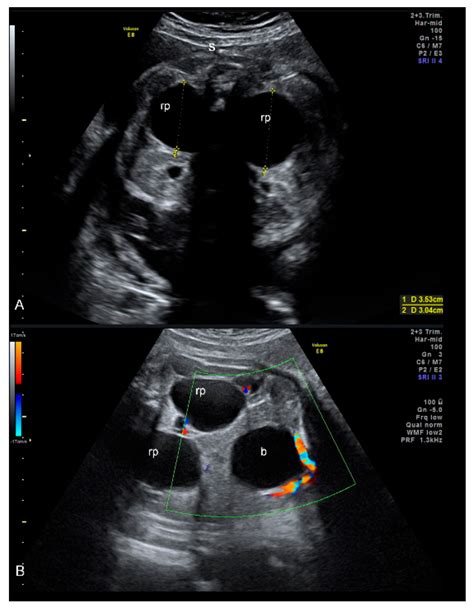

During the second-trimester anatomy ultrasound, typically performed between 18 and 22 weeks of gestation, the sonographer meticulously examines all the organs of the fetus to ensure proper development. Pyelectasis of fetus is identified when the renal pelvis measures slightly larger than the established clinical threshold. In most medical guidelines, a measurement of 4mm to 7mm is considered mild, while measurements above 7mm or 10mm may warrant closer monitoring.

To distinguish between a normal variation and a condition requiring medical follow-up, healthcare providers rely on standardized measurements. The severity is generally categorized based on the diameter of the renal pelvis in the anterior-posterior (AP) view.